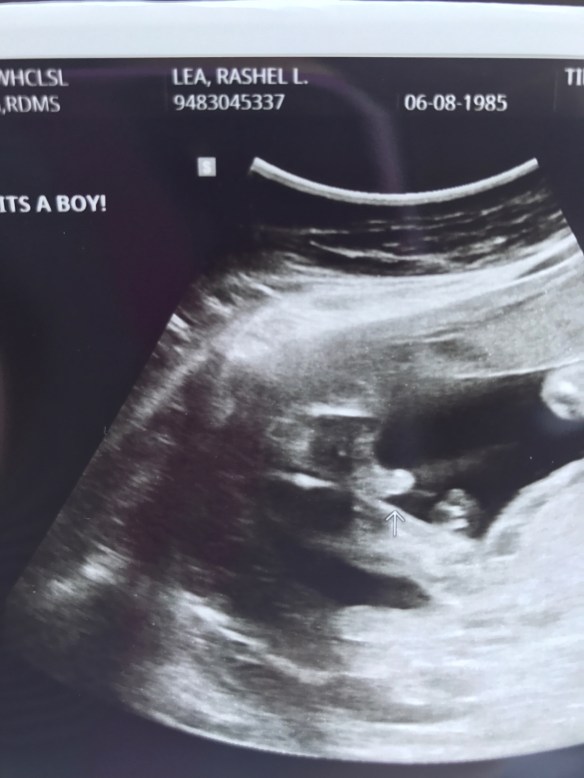

Well on Friday we had our big ultrasound! J and K flew into town on Wednesday so it was nice spending a bit of time with them! We spent time in a old town st. Charles and then had dinner at our house where we had a buffet of st Louis! We had pork steaks, imos, toasted ravioli, white castles and gooey butter cake! It was a success! My kids thought it was the best dinner ever haha. So on Friday we did the whole ultrasound and baby B really was active but didn’t want to roll over so I’ll have to do another ultrasound at 28 weeks to get a few more pictures of the heart. Everything looked perfect though! Baby B is growing well and is about 12oz I believe they said! So when they finally got to the sex of the baby I for one was shocked 😳! Turns out it’s a BOY!!! now let me explain why I was so surprised. After we did our transfer where they put the baby in the dr said well she’s all in there! I was pretty mad thinking he told me the sex of the baby after it was decided we didn’t want to know! So needless to say this whole time I thought I already knew it was a girl and I just had to keep it a secret! They said it was a boy and I just couldn’t believe it! I’m so very excited for J and K. So now we are already at the half way point so now it gets more exciting each week!!!! Oh and baby B is moving a lot more now and is definitely getting stronger. He really loves waking up at around 4 am to kick and play me not so much. Good thing I like this little guy! I’m glad he’s letting me know he is there even if it is too early. So here is what baby B is up to this week!!!

Curious about whether that melon-sized belly has a boy or a girl inside? Now’s your chance to take a peek! Though the external genitals in both male and female fetuses still have a way to grow, you’ll be able to find out your baby’s gender via the second trimester ultrasound , usually scheduled for anytime between 18 and 20 weeks. This routine exam gives your practitioner a chance to see how things are going in there (and wow, are they going!). If you’re carrying a girl, your baby’s uterus is fully formed this week and the vaginal canal is starting its development (which means that in a few decades, you might be a grandma!). Your little girl also has primitive eggs in tiny ovaries now, seven million of them. By birth, that number will be down to two million. If your fetus is a boy, the testicles have begun their descent this week, though they’re still in the abdomen waiting for the scrotum to finish growing so they’ll have a place to go in a few weeks.